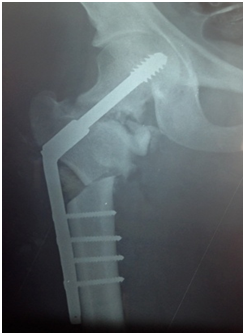

A radiograph of the pelvis revealed a primary non union fracture neck of femur (Figure 1). On MRI, it was found that the femoral head was viable (Figure 2).

Figure 2 MRI of pelvis showing viability of Right femoral head.